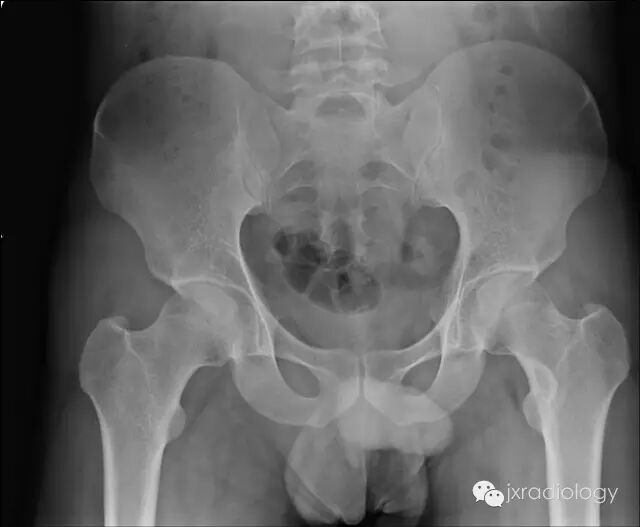

X线检查示骨纤维异常增殖症(Fibrous dysplasia ,FD)病变位于髓腔内,多见于骨干,病变区域多透亮,很少情况下出现高密度影(基质钙沉积时可出现),正常的骨小梁结构消失,代之以细颗粒“毛玻璃”样,有时病变周围的硬化骨带则可组成“果皮征”(rind sign)。

任何骨骼均有可能受累,但纤维异常增殖症多侵犯股骨(尤其是股骨颈)、胫骨、骨盆、肋骨、颅骨、头面骨及椎体。约 70%-80% 的患者为单处骨骼发病,而 20%-30% 患者为多处部位发病,其中两种较著名的多发纤维异常增殖症业已被报道(McCune-Albright 综合征和 Mazabraud 综合征)。